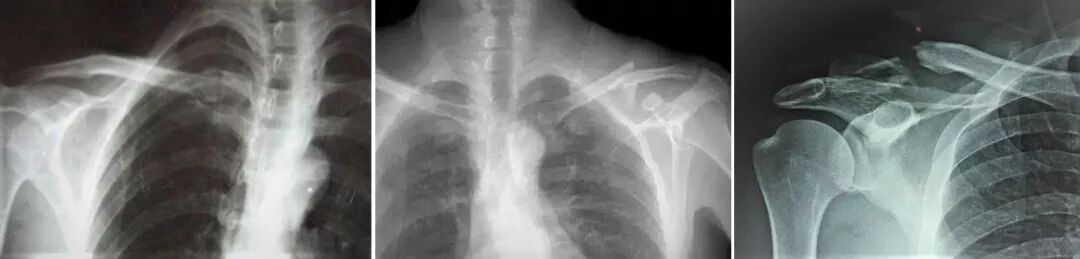

▲锁骨近端、中段、远端骨折

我院上肢创伤科部分患者术前术后对比图